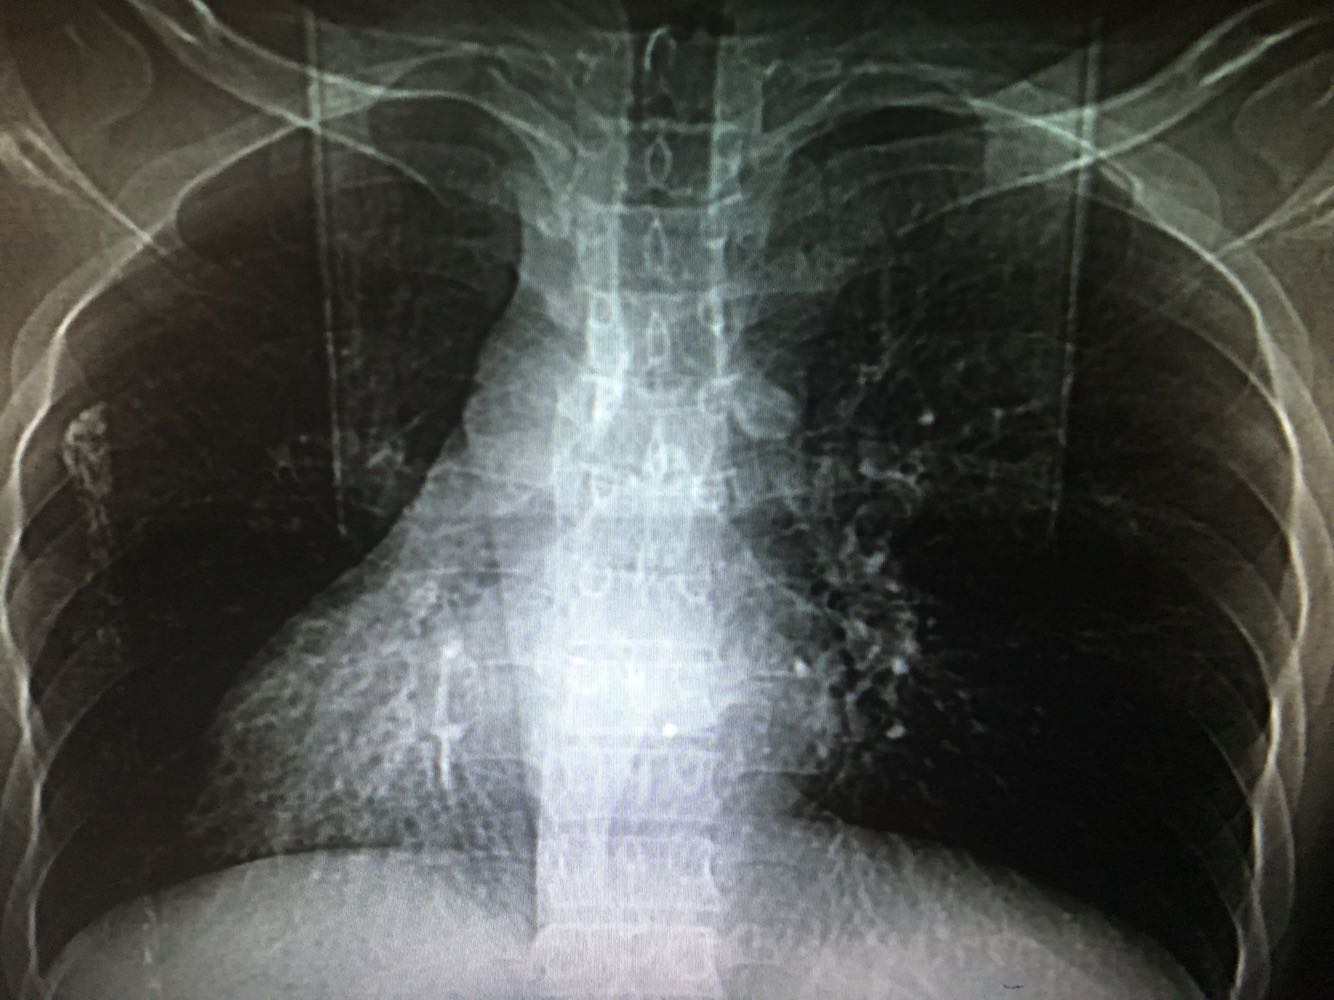

1、患者,男,33岁                                  2、主诉:咯血2天 3、现病史:患者2天前体力后出现咯血,色泽鲜红,量约100ml,无异味及异物,无胸闷气促、无头晕乏力、无腹痛腹泻、无黑曚晕厥等不适,就诊外院,查BP:130/85mmHg,血常规WBC 8.09*10^9/L,N%64.7%,HB147g/L,PLT180*10^9/L。胸部CT:两肺下叶及左肺上叶舌段支气管扩张。未予特殊处理,嘱休息随访,患者回家2小时后再次出现上述症状,呕吐鲜红色血伴血块,遂就诊我院,为求进一步诊疗,收治入院。 4、既往史:既往有支气管扩张、右位心、慢性鼻炎病史,否认高血压、糖尿病,否认乙肝结核等传染病史,否认食物、药物过敏史

查体:神清,精神可,T36.8℃,BP:130/85mmHg,对答切题,双侧瞳孔等大等圆,直径3mm,对光反射存在,皮肤及巩膜无黄染,无贫血貌,浅表淋巴结未及肿大,颈软,气管居中,双肺呼吸音清,可闻及湿罗音,心率80次/分,律齐,无杂音,腹平软,无压痛,无反跳痛及肌紧张,肝脾肋下未及,未见明显胃肠型蠕动波,肠鸣4次/分,未及明显肿块,肝肾叩击痛(-),移动性浊音阴性,双下肢无水肿,神经系统检查(-)

诊断:支气管扩张咯血,右位心,慢性鼻炎                                                              治疗:入院后完善检查,予抗感染,保肝,护胃,止血、化痰、补液等对症支持治疗。